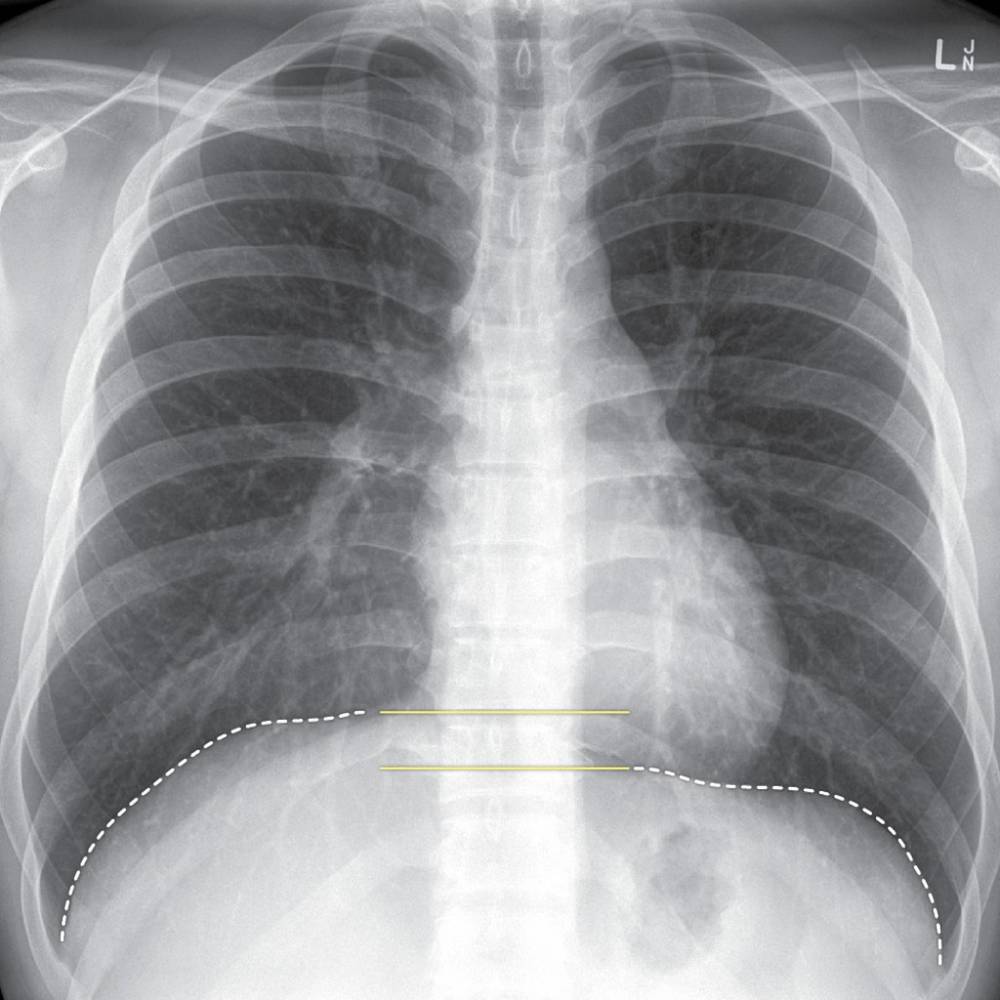

Berkongsi pengalaman menjaga pesakit kanser, Remaja berkesempatan bertemu dengan Dato’ Hans Isaac yang pernah menjaga mendiang ibunya yang disahkan menghidap kanser paru-paru kira-kira 10 tahun yang lalu.